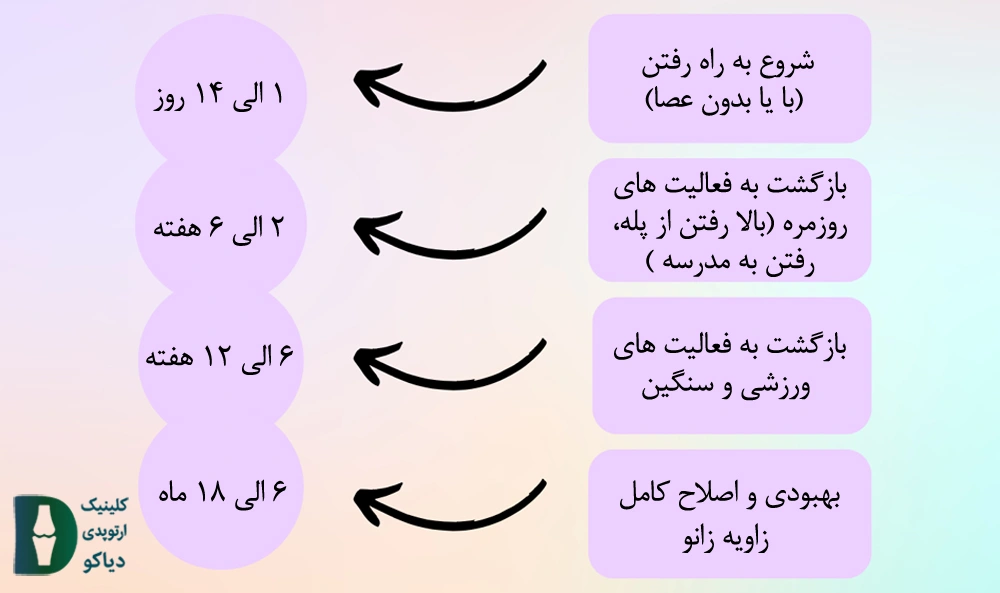

اگر چه زمان دقیق بازگشت به فعالیت به عواملی نظیر ویژگیهای بدنی فرد و … بستگی دارد. اما با این حال در شکل زیر زمان بازگشت به فعالیت در مراحل مختلف بهبودی به نمایش درآمده است:

در شکل زیر زمان بازگشت به فعالیتهای مختلف شرح داده شده است. البته در نظر داشته باشید مدت زمان دقیق هریک از موارد زیر به خصوصیات بدنی فرد، سن و دیگر عوامل بستگی دارد.

زمان بازگشت به فعالیت را می توانید در شکل زیر مشاهده نمایید:

زمان بازگشت به فعالیت پس از انجام جراحی تعویض مفصل زانو به عواملی نظیر قدرت بازیابی فرد، مهارت پزشک و … بستگی دارد. با این حال در شکل زیر مدت زمان تقریبی بازگشت به فعالیتهای مختلف شرح داده شده است: